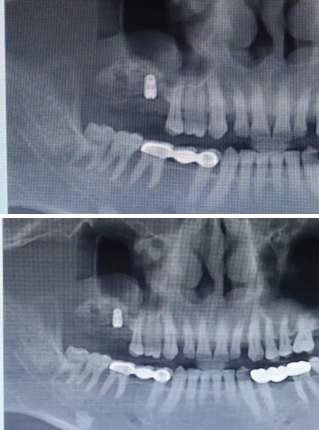

【病例分享】上頜竇大囊腫外提升